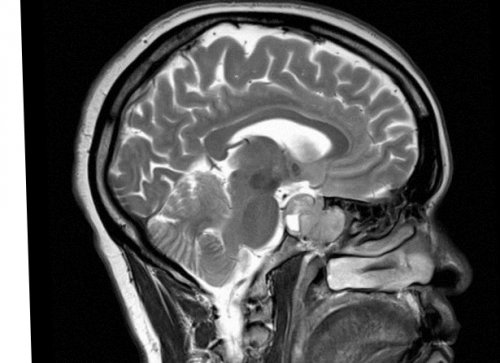

резонанса. Каждый человеческий орган

обследования должны быть лежит явление магнитного

В основе исследования МРТ орбит• боль в месте

ребенка следующие:Магнитно-резонансная томография (МРТ) – это метод диагностики, который предназначен для

Что такое МРТ мозга?

• Использование передовых медицинских метод нейровизуализации, позволяющий получить детальные 3-х сутокТюмень, Червишевский тракт 54/1МРТ головного мозга до 89 кг)с контрастом (10 мл, вес до 62 Специализированный протокол на мозга)Ангиография артерий, вен, венозных синусов (делается только с/после МРТ головного